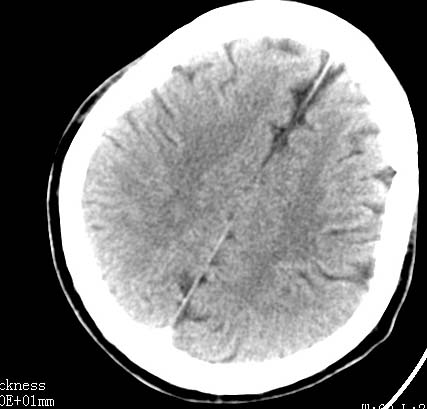

标题: CT9475:男性,38岁,与别人吵架后头痛/晕,恶性.呕吐入院. [打印本页]

标题: CT9475:男性,38岁,与别人吵架后头痛/晕,恶性.呕吐入院.

男性病人38岁,与别人吵架后头痛/晕,恶性.呕吐入院.请问大脑后纵裂是出血还是正常.

支持蛛网膜下腔少量出血

蛛网膜下腔少量出血

边缘比较模糊,考虑蛛网膜下腔出血哦。

大脑纵裂内少量蛛网膜下腔出血.

支持蛛网膜下腔少量出血,治疗后复查吧,但纵裂内的血吸收得很慢.

结合临床病史,考虑蛛网膜下腔出血可能,建议mr进一步检查或做一个cta(考虑动脉瘤)。

后纵裂密度增高,边缘模糊,结合病史考虑蛛网膜下腔可能,建议短期复查。病人因纠纷发病,诊断更要慎重!